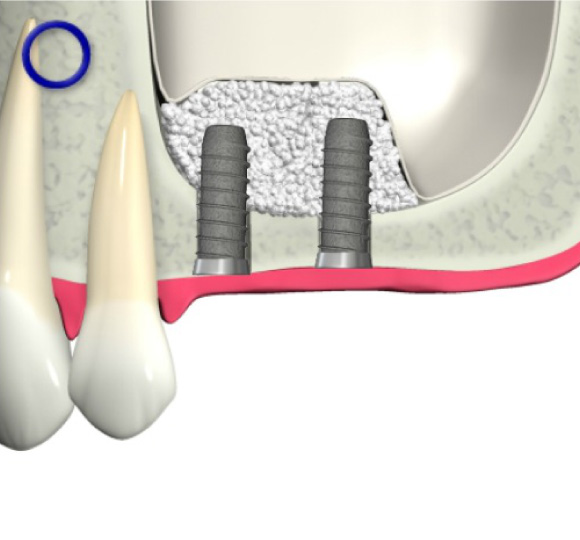

骨が少ない場合①

歯槽骨が吸収し、上顎洞が下がっています。このままではインプラントが突き抜けてしまうためインプラントはできません。

上顎洞が上に押し上げられ、インプラントを埋入するスペースができました。骨の材料も充填されているのでインプラントは安定します。

ソケットリフト方法

歯肉を切開します。

骨をドリルで切削します。

上顎洞の壁を押し上げます。

骨の材料を充填します。

インプラントを埋入します。

骨が少ない場合②

インプラントを支えるための歯槽骨が十分でないためインプラントはできません。

インプラントを支えるための歯槽骨が作られました。インプラントを埋入する事が出来ます。

GBR法